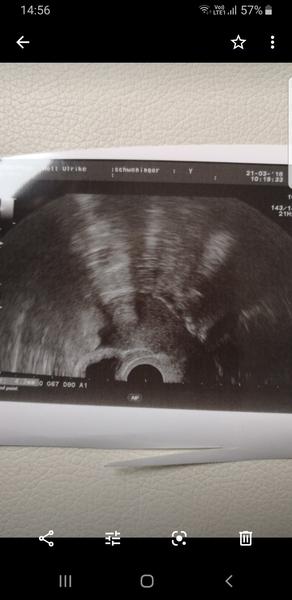

Dobrý deň. Prosím vás mal niekto skúsenosť že mal hcg 1000 som 4tt+3 a nič ešte nie je vidno iba zvýšená sliznica? Doktorka má postrasila že to môže byt mimomaternicove. V stredu 19.6.19 som bola na krv hcg som mala 500 dnes som bola 21.6.19 a hcg som mala 1000. Je to podľa vás v poriadku? Ako viem že doktorka vie najlepšie ale chcem vedieť či to niektorá z vás takto nemala

@shilla23 lenže zase keď som bola predtým na usg keď som bola tehotná (potratila som ] tak v ambulancii kde mám svoju gynekologickú nevidela nič a keď som šla na pohotovosť lebo som začala špiniť tak videla už gestacny váčok na druhý deň. Aj mi povedala doktorka na pohotovosti že v ambulanciách majú slabšie usg. Čiže možno to bude aj tým že to tak vidno.

Ja som bola na sone 5+4 a tiež tam nič nebolo, potom o tri tyždne normalne plod aj akcia srdca. A v pondelok nebudeš mať 1500, pretože hcg sa zdvojnasobuje každych 48hodin. Čiže streda 500, piatok 1000, nedela 2000, utorok 4000,....